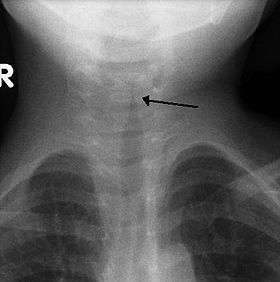

![]() The steeple sign as seen on an AP neck X-ray of a child with croup | |

A frontal X-ray of the neck is not routinely performed,[3] but if it is done, it may show a characteristic narrowing of the trachea, called the steeple sign, because of the subglottic stenosis, which is similar to a steeple in shape. The steeple sign is suggestive of the diagnosis, but is absent in half of cases.[10]